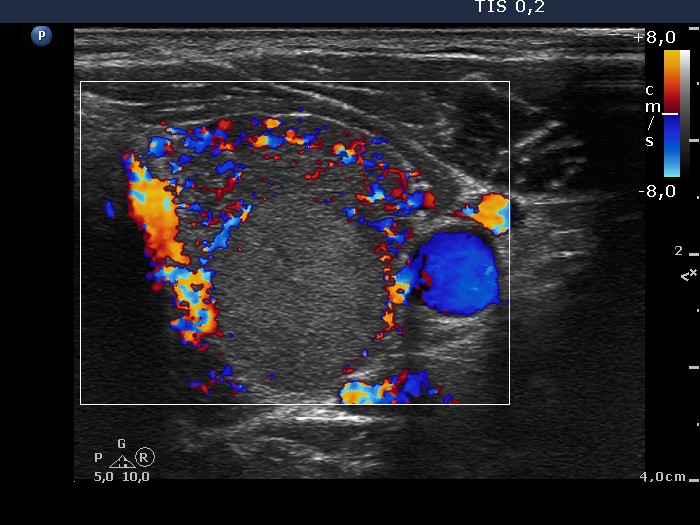

Consecutively operated patients with autoimmune thyroid disease - case 37 (conp 033) (ultrasonographic picture 8)

Left lobe, transverse scan, color Doppler mode. This pattern pretends as to the nodule had perinodular blood flow, while in fact only the extranodular part of the lobe presents markedly increased vascularization. The nodule displays neither perinodular nor intranodular blood flow.